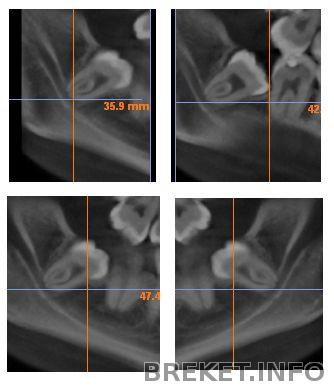

Вот, нашла фотки с томограммы, видно что корни прям чуть ли не в нерве...

Орт: за счет удаления 4ки на ВЧ появилось место, поэтому удалять 8ку нет необходимости. На НЧ показано удаление 4ок (на момент консультации. Позже мы решили обойтись удалением одной 5ки), места будет достаточно, 8ки удалять не нужно. Стоит добавить, что корнями нижние лежат прям на нерве, а "угол челюсти у меня маленький, удаление будет мерзопакостным".

Но нижние... Угол челюсти маленький - а значит, либо челюсть еле открыта, освобождая доступ к зубу но так никаким инструментом не подлезешь, либо рот открыть шире чтоб можно было подлезть - но так к зубу не подступиться... Плюс корни на нерве лежат, что чревато его повреждением (как это хреново можно не говорить, да?)